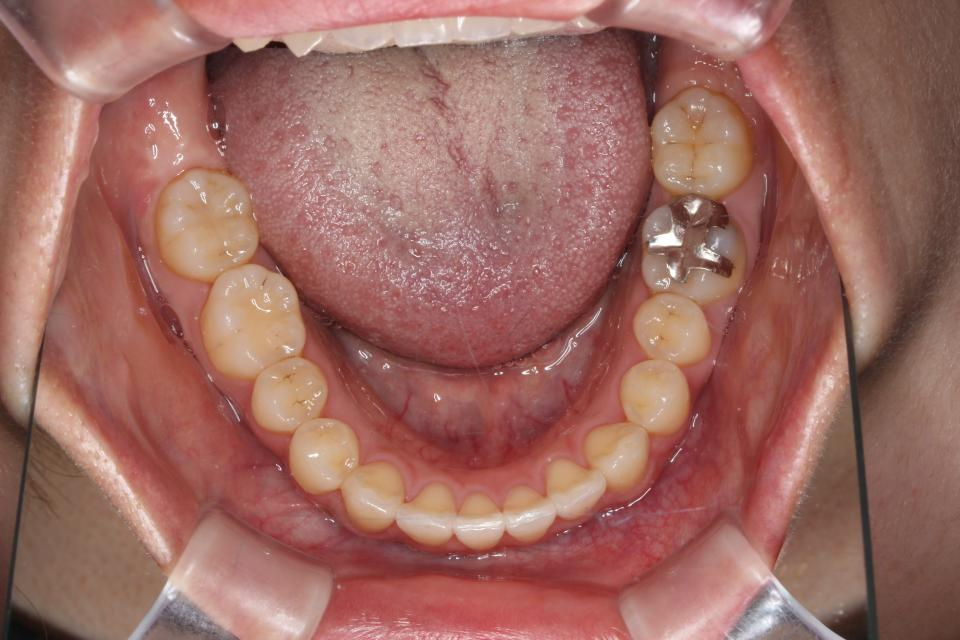

矯正治療後

現在は歯を動かす治療は終了し、マウスピース型のリテーナーをつけて

定期的にチェックしています。